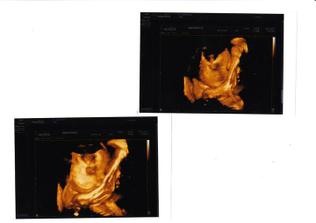

Malý 34. týden

Obličejík s ručkou